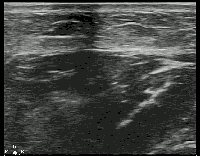

Soft Tissue - Compression for Abscess Identification

While typically an abscess will appear as a hypoechoic fluid filled structure, sometimes it can be missed as its echotexture is similar to other surrounding soft tissue structures. To improve sensitivity, gentle compression should be applied to identify a subtle abscess as seen above. Image obtained from Ultrasound of the Week.